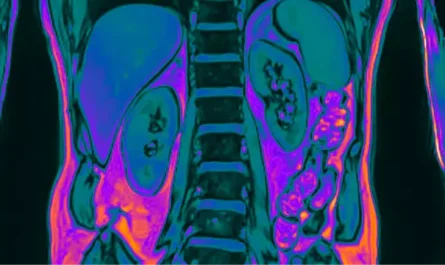

A team at the Netherlands Cancer Institute first made the unexpected find in September 2020 while examining prostate cancer patients using advanced imaging techniques. (NKI)

They performed PET/CT scans using a tracer that highlights prostate cancer cells (via the protein PSMA). To their surprise, in the region behind the nose and throat, two areas glowed more strongly than expected. Further investigation showed these areas had the characteristics of salivary gland tissue. (Sci.News: Breaking Science News)

- They only became visible due to very sensitive molecular imaging (PSMA PET/CT), which highlighted unexpected uptake in those regions. (Sci.News: Breaking Science News)

Featured Image Credit: Netherlands Cancer Institute